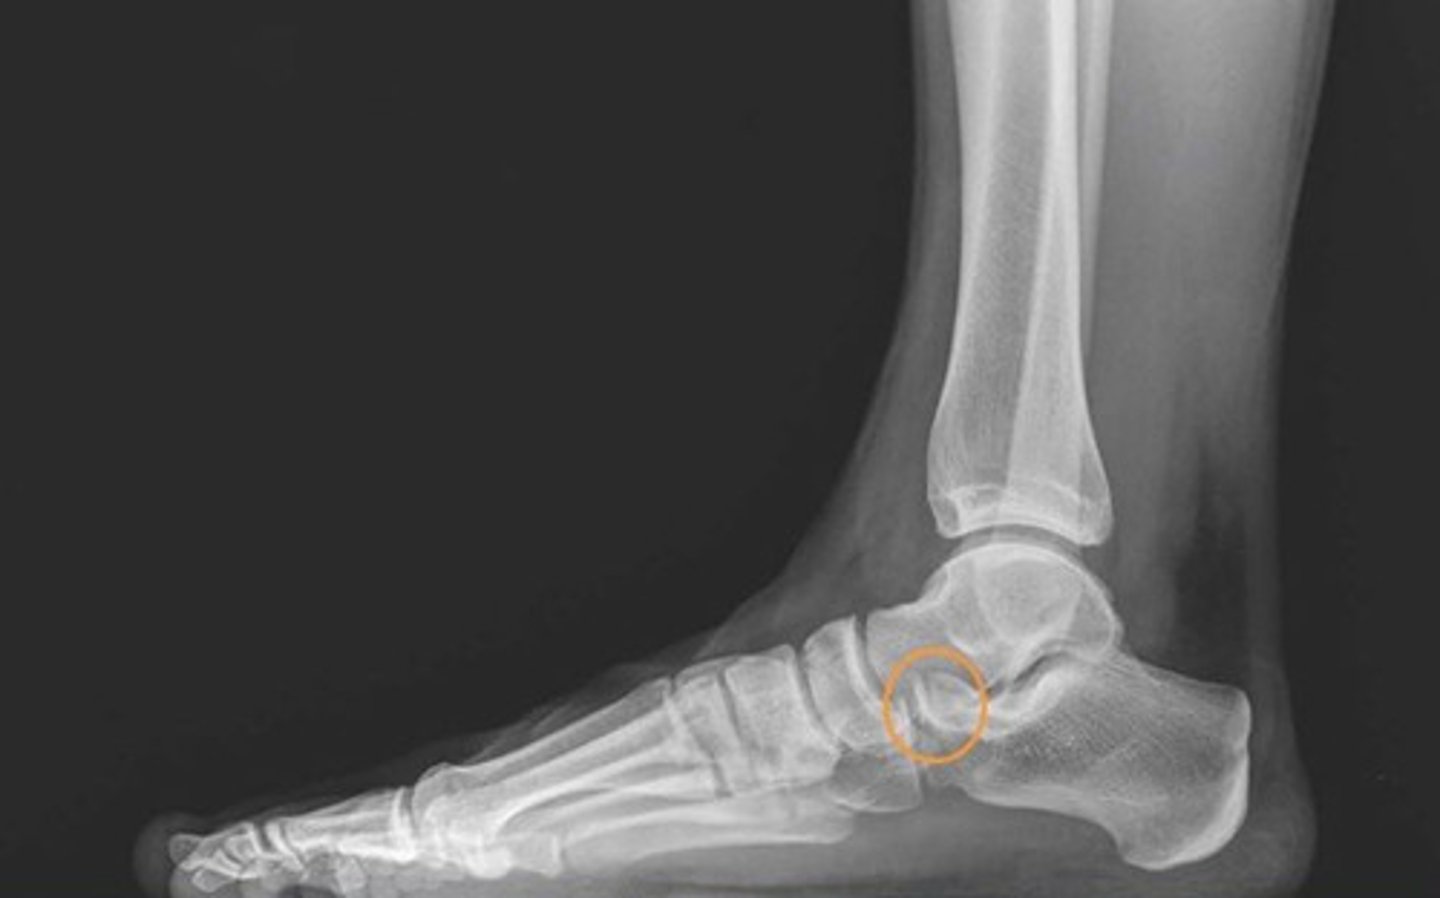

what radiograph view is shown here?

lateral

3 multiple choice options

what do the orange circles in these radiographs indicate about the patient's injury to the anterior process of the calcaneus?

avulsion fracture

2 multiple choice options

after revealing a non-displaced fracture of the anterior process of the calcaneus, which of the following options will allow for the structure to heal?

controlled ankle movement (CAM) walking boot